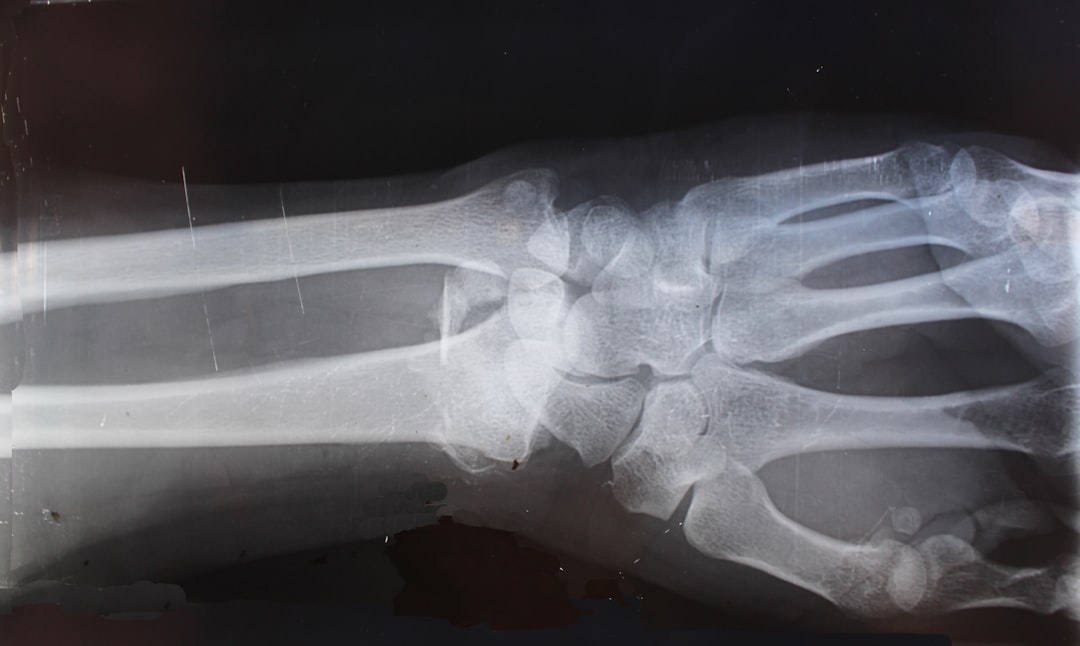

관절염은 관절에 염증이 생기는 질환으로, 통증과 불편함을 유발합니다. 관절염에 도움이 되는 약은 이러한 증상을 완화시키고 관절의 기능을 회복하는 데 큰 역할을 합니다. 가장 일반적인 약물은 비스테로이드성 항염증제(NSAIDs)와 질병 수정 항류마티스 약물(DMARDs)입니다. 이러한 약물들은 염증을 줄여 줄뿐만 아니라, 통증을 완화하고 이동성을 개선하는 데 도움을 줍니다.

관절염의 원인은 다양합니다. 유전적 요인, 환경적 요인, 감염 등이 복합적으로 작용하며, 생리학적인 변화가 일어날 수 있죠. 따라서, 관절염에 도움이 되는 약을 사용하기에 앞서 반드시 전문 의료인의 상담이 필요합니다. 약물의 효과와 부작용, 그리고 개인의 상태에 맞는 최적의 처방은 전문가에게 얻어야 합니다.

관절염의 증상은 개인마다 다른데, 일부는 가벼운 통증과 불편함을 느끼는 반면, 다른 일부는 심각한 통증으로 일상 생활이 어려울 수 있습니다. 이런 이유로, 관절염에 도움이 되는 약을 올바르게 선택하는 것이 중요합니다. 여러 약물들이 있어 혼란스러울 수 있지만, 각 약물의 특성과 효과를 이해하면 더 나은 선택을 할 수 있습니다.